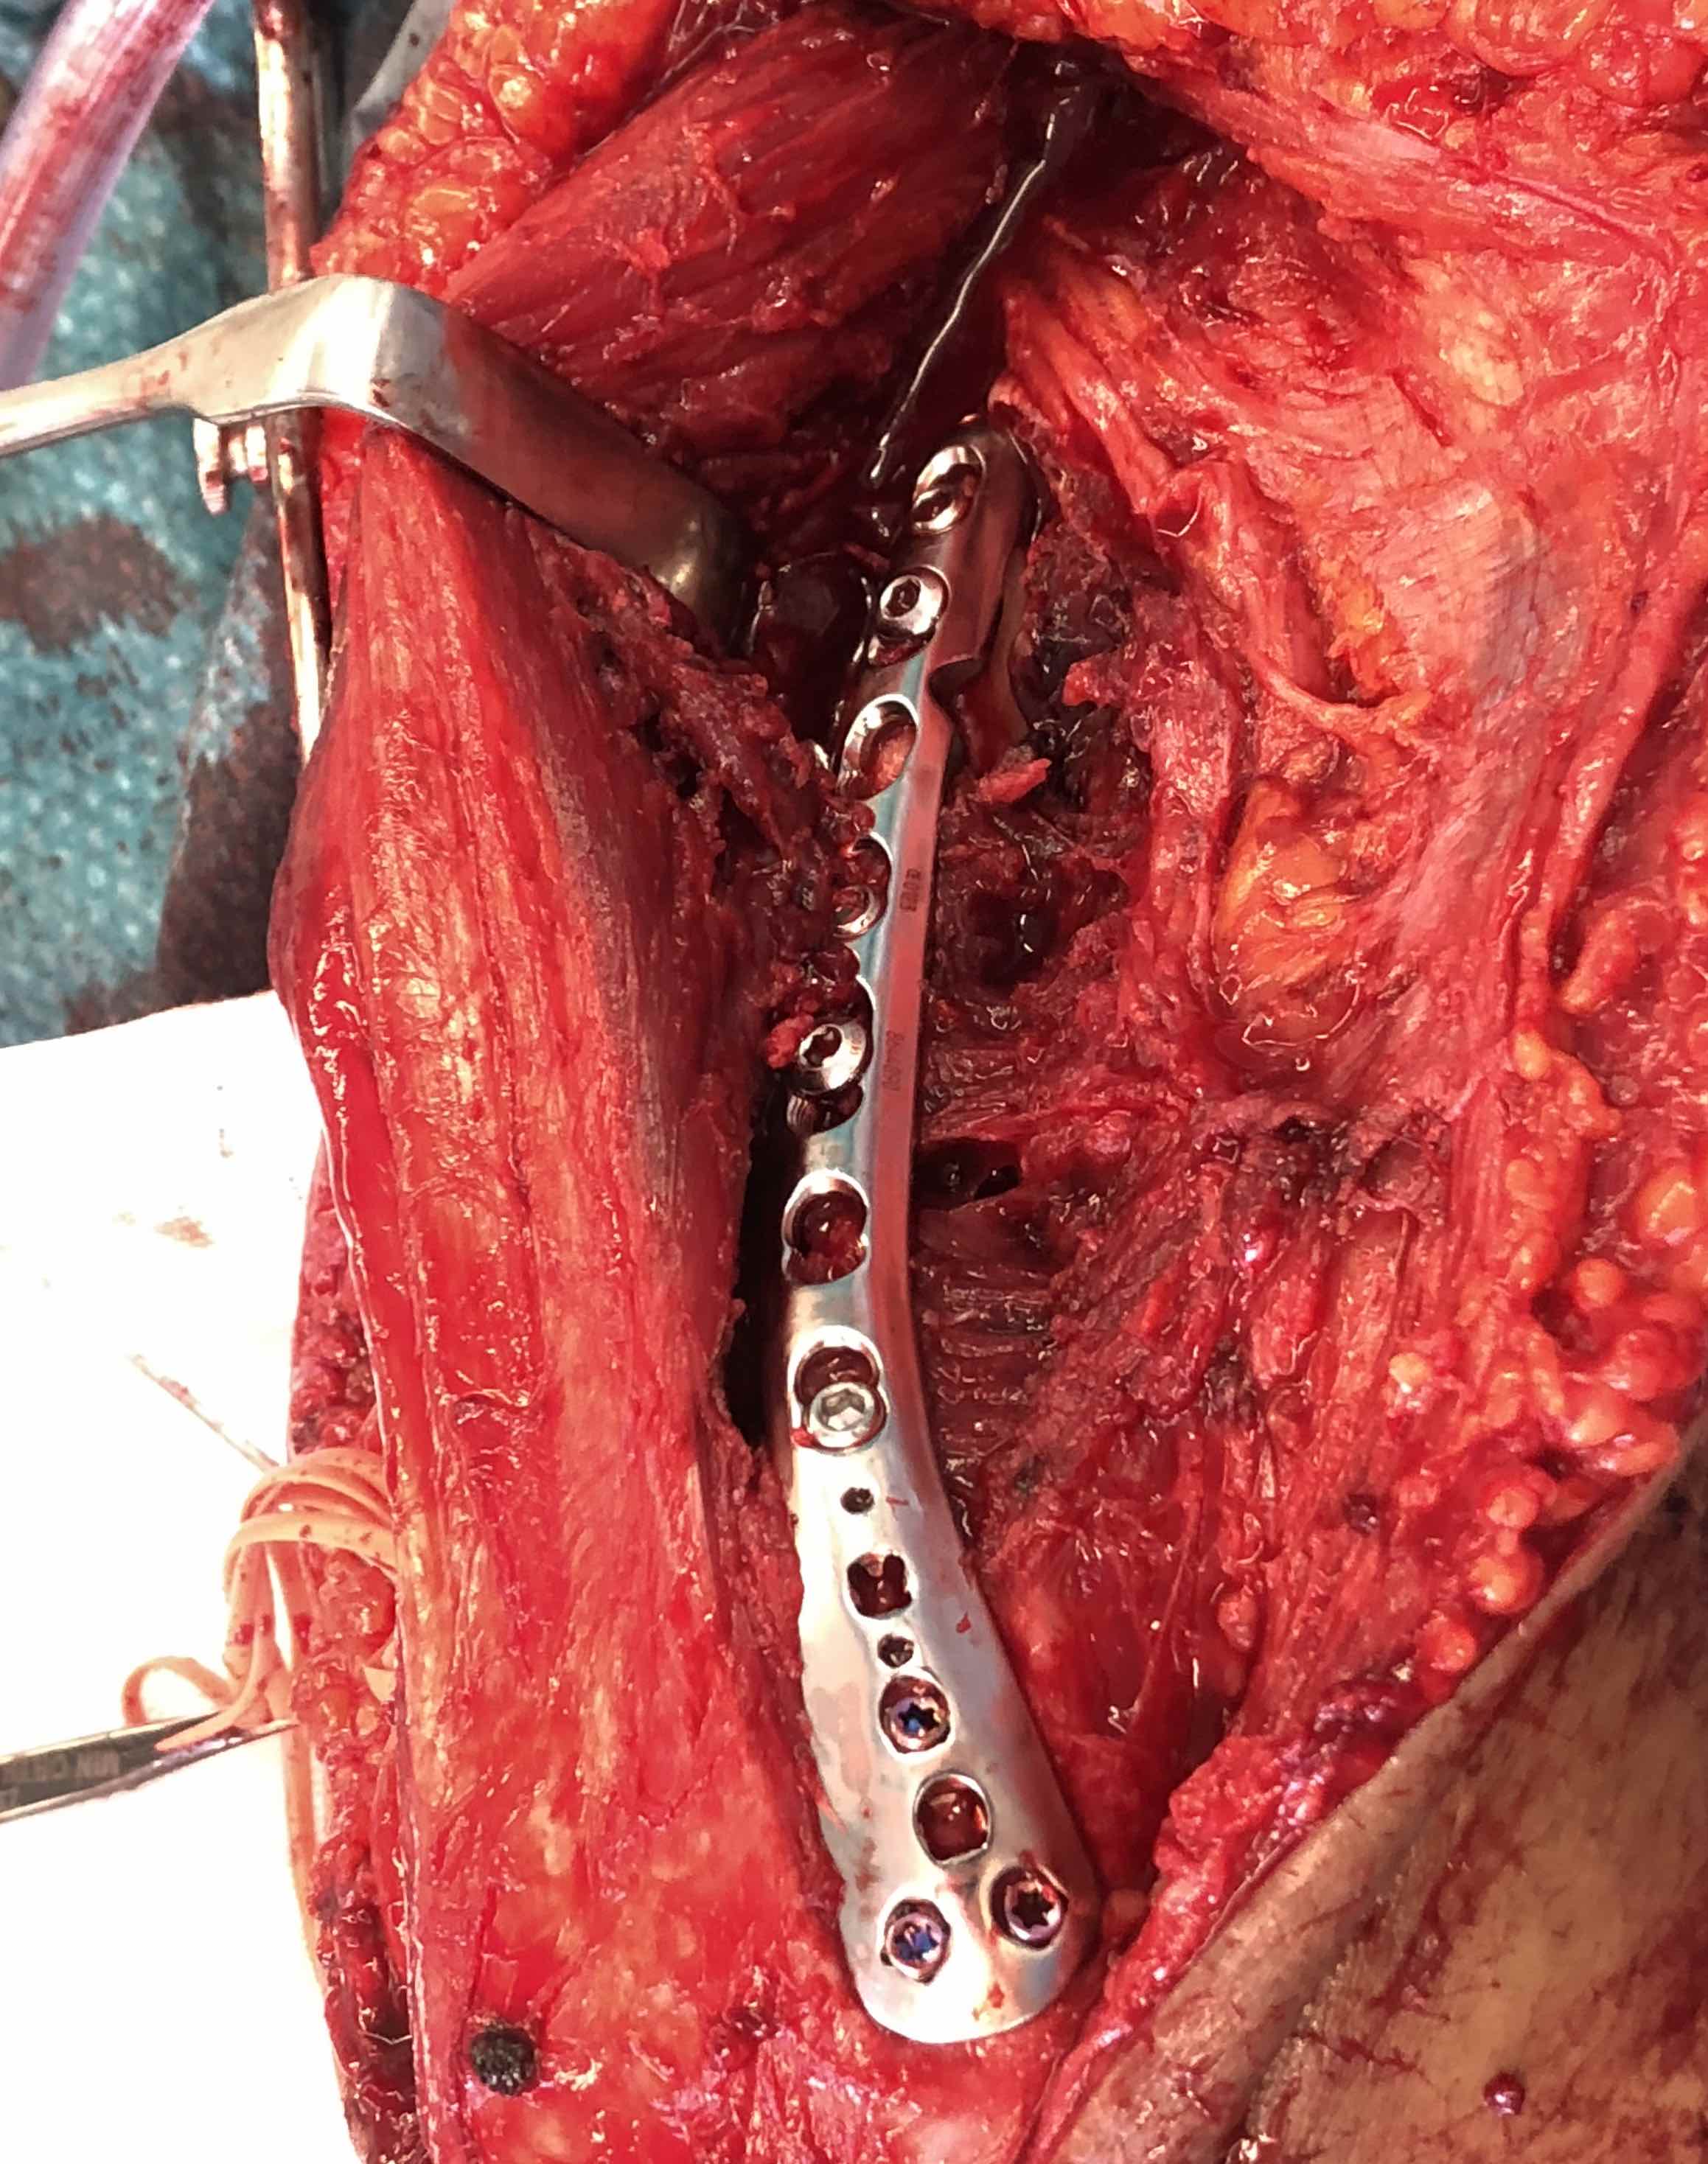

ORIF with plates

Fixation techniques

Options

Precontoured anatomical plates

Parallel plates v perpendicular plates

Parallel plates - medial plate on medial column and lateral plate on lateral column

Perpendicular plates - plates at 90 degrees, with lateral plate posterior